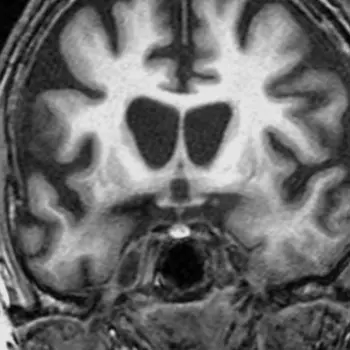

3. 헌팅턴병

헌팅턴병은 신경계에 영향을 주는 희귀한 유전성 질환으로, 주로 중년 이후에 증상이 나타나며 서서히 악화되는 특징을 가지고 있습니다.

이 질환은 HTT 유전자에 이상이 있는 경우 발생하며, 이 유전자는 헌팅턴 단백질 생성에 영향을 미칩니다.

일반적으로 이 단백질은 뇌의 신경세포에서 중요한 기능을 하지만, 헌팅턴병 환자의 경우 이 단백질이 비정상적으로 증가하여 뇌세포의 작용을 저해하고 세포 사망을 유발합니다.

헌팅턴병의 주요 특징은 운동 기능 이상, 인지 기능 저하, 정서적 문제 등이 있습니다.

이 질환은 HTT 유전자의 이상으로 인해 헌팅턴 단백질 생성이 비정상적으로 증가하여 뇌세포 기능을 저해하고 세포 사망을 유발합니다.